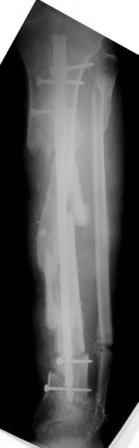

Коллеги!Позвольте продолжить обсуждение темы «ложный сустав левой голени.» Больной К 45 лет, начало см. http://www.weborto.net/forum/1228422607/ И рассказать о результатах проделанной работы. Остановились на следующей тактике 1) Наложить Аппарат Илизарова. В аппарате восстановить оси трех смещенных относительно друг-друга фрагментов большеберцовой кости. Устранить вальгусную деформацию дистального отдела большеберцовой кости. Что и было выполнено. - Была выполнена репозиция в аппарате (рис1) 2) После репозиции более очевидна стала проблема дефекта кости в верхней трети голени, два фрагмента свободно лежат. Остановились на варианте перехода на интрамедуллярный синтез стержнем с покрытием костный цемент+ванкомимцин и замещении дефекта с помощью транспорта фрагмента (рис 2) 3) Третьим этапом наложили модуль на промежуточный фрагмент.(рис 3) И начали его транспорт на стержне в проксимальном направлении. (рис 3 а) Надеемся что «вырастет» регенерат в дистальном отделе, а в проксимальном отделе фрагмент «упрется» и прирастет. Хочу сказать слова благодарности за обсуждение на форуме этого случая. Особые слова благодарности Иванову Павлу Анатольевичу!!! Он помогал Словом, а самое главное делом. Приезжал, оперировал! За что ему нижайший поклон! С ув Коробушкин Г